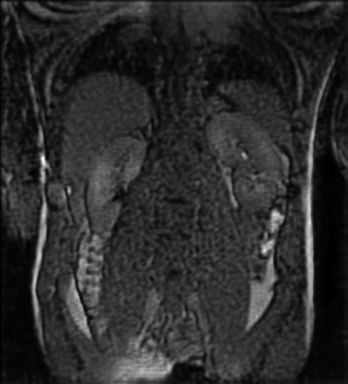

Tables 1 and 2 show our quantitative results: PSNR between the style (image we want to transfer style from) and generated image, SSIM and MS-SSIM between the content (image we want to take structure from) and generated image and finally, our proposed weighted SSIMs. For each style transfer direction and metric, our method consistently outperforms the other approaches. Figures 2 and 3 qualitatively highlight the good results of our method on 2D and 3D datasets. In addition, quantitative results on both figures show that our proposed metric preserves qualitative ordering of results for both style and content. In comparison, metrics such as SSIM struggle to accurately correlate to visual results.

Qualitative evaluation shows that the proposed method leads to sharper images, better content preservation, better localised CE and realistic MRI appearance. Quantitatively, we outperform the other algorithms with each metric, for each style transfer direction. While we expected that adding CE to images would be an easier task than removing CE, we found that for both tasks the method exhibits similarly performing quantitative and qualitative results. The results for style transfer with the kidney data show that when there is clear CE, it is easier to perform style transfer in both directions. However, when style transfer is performed on the prostate data, the model struggles in comparison to the kidney data. This may be due to the enhancement of the prostate being less defined than the kidney data. In figure 3(b), we can see the prostate with CE. Compared to figure 2(b) showing kidneys with CE, it is harder to determine the edges. The two original images shown in figures 3(a) and 3(b) are clear and easy to see some edges of prostate, in other images, it is harder to see the edges of the prostate.